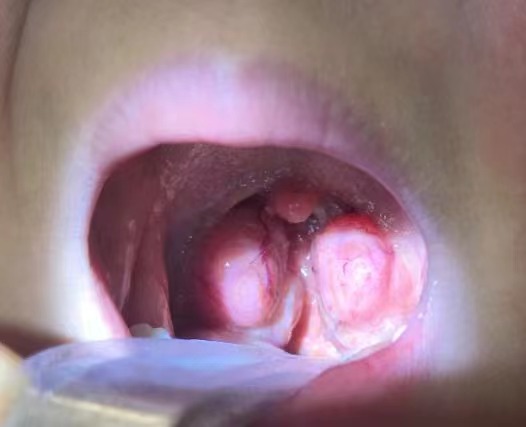

我家闺女扁桃体肿大越来越严重,这月已经是第二次发烧了,烧到39度。去年就被确诊是二度肿大,今年更厉害,怕是有三度了。白天晚上都是张嘴呼吸。看着就心疼,试了好多办法都没有用。求一个安全、快速的解决的方法!!!

感谢,你的方法真的是很管用,才不到一个月孩子扁桃体就已经好的小多了,上图给大家看看,另外,老师人也非常nice,这么好的方法,推荐大家也试试,再一次感谢!